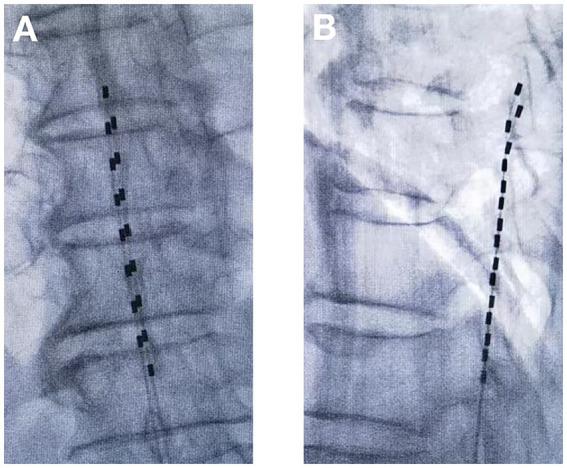

Zoster-associated pain (ZAP) is a common complication after herpes zoster infection. In recent years, conventional temporary dorsal column stimulation (tDCS) has been widely used nationally and internationally as a safe and effective minimally invasive treatment for ZAP. It has also been shown that temporary dorsal nerve root stimulation (tDNRS) may also be an effective treatment for ZAP. However, there is no direct clinical comparison between the newer tDNRS and the conventional tDCS.

To compare the procedure time, radiation dose, efficacy and cost of the tDNRS and tDCS for the treatment of ZAP. And the complications of the two surgical modalities were recorded.

Eighty patients with ZAP who attended the pain department of the Second Affiliated Hospital of Guangxi Medical University from January 2022 to July 2023 were selected. They were divided into tDNRS group ( = 40) and tDCS group ( = 40) by using random number table method. The operation time, radiation dose, number of electrodes used, cost of medical consumables, and number of postoperative electrical stimulation adjustments were recorded for each case, and the patients' pain level, sleep quality, quality of life, and overall efficacy were analysed and compared at preoperative (T0), 1 week (T1), 1 month (T2), 2 months (T3) and 3 months (T4) after the operation.

A total of 76 patients were finally enrolled, 38 in the tDNRS group and 38 in the tDCS group. During the 3-month follow-up period, all patients showed a significant decrease in Numerical Rating Scale (NRS) and Pittsburgh Sleep Quality Index (PQSI) scores and a significant increase in quality of life (QL-Index scale) scores after treatment with both methods. And there was no statistically significant difference between the two methods. However, patients who received tDNRS had a significantly shorter operative time and less intraoperative radiation exposure than those who received tDCS ( < 0.0001), and the mean number of postoperative stimulation parameter adjustments and the cost of medical consumables were significantly lower than those in the tDCS group ( < 0.0001).

Both tDNRS and tDCS were effective in the treatment of ZAP, but tDNRS had the advantages of more precise coverage, shorter procedure time, less radiation exposure, fewer electrical stimulation adjustments, and lower cost.